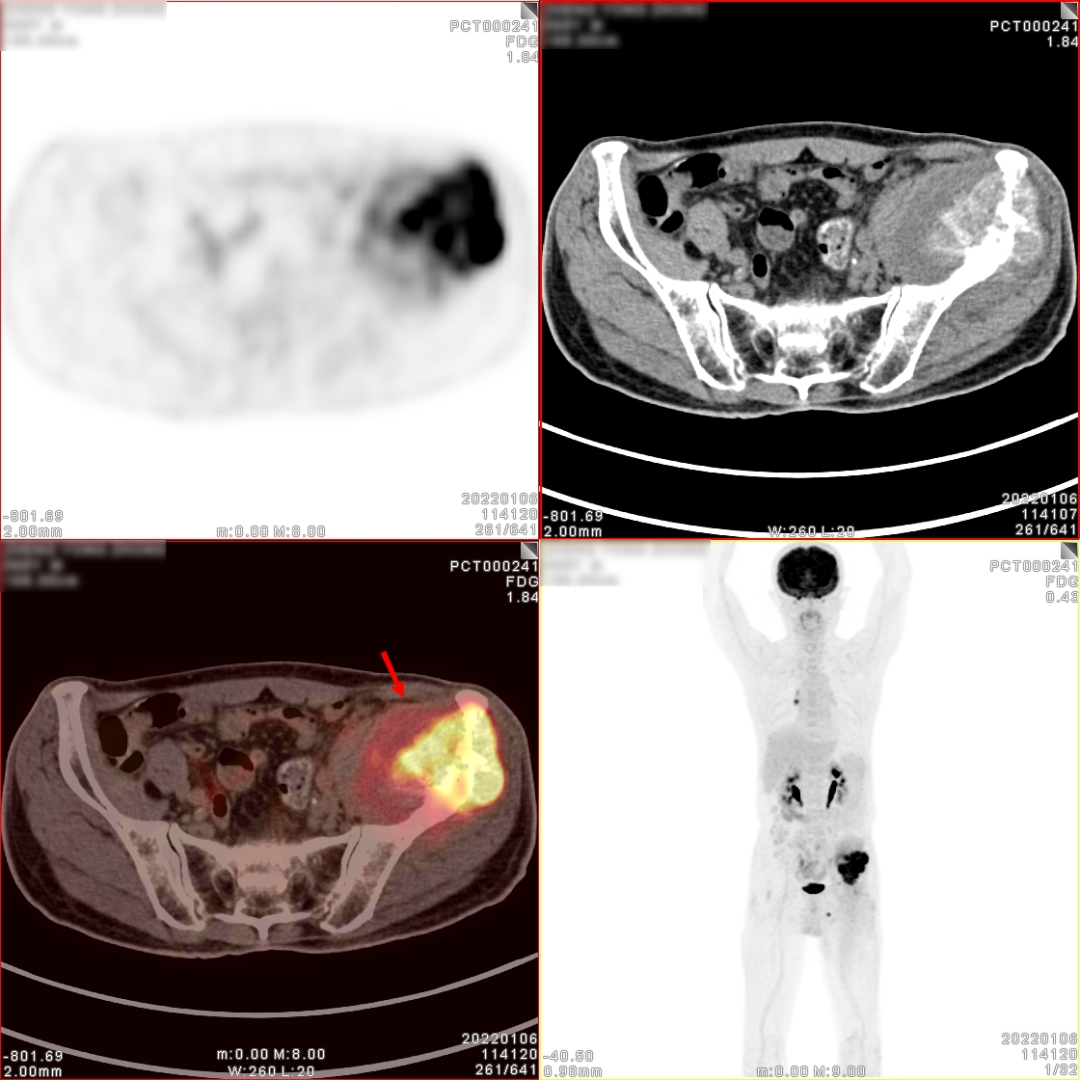

髋关节MR检查图像

图片

MR表现:

左侧髂骨骨质破坏,累及髋臼,形成巨大软组织肿块,其最大径大致约 10.6cmx7.6cmx7.6cm;与邻近肌肉相比:T2WI肿块下部呈稍高信号,外 上部呈高信号,T1WI呈等高信号,其中可见斑点状高信号;DWI高b值, 肿块下部呈不规则高信号。瘤周肌肉可见水肿;左侧腰大肌前移。膀胱直肠窝可见少许液性信号影。

MR诊断:

1、左侧髂骨改变,结合病史,考虑转移瘤。

2、盆腔少许积液。